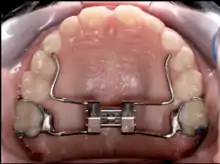

Upper and lower jaw functional expanders

A typical treatment for incorrectly positioned teeth (malocclusion) takes from one to two years, with braces being adjusted every four to 10 weeks by orthodontists,[29] while university-trained dental specialists are versed in the prevention, diagnosis, and treatment of dental and facial irregularities. Orthodontists offer a wide range of treatment options to straighten crooked teeth, fix irregular bites, and align the jaws correctly.[30] There are many ways to adjust malocclusion. In growing patients, there are more options to treat skeletal discrepancies, either by promoting or restricting growth using functional appliances, orthodontic headgear, or a reverse pull facemask. Most orthodontic work begins in the early permanent dentition stage before skeletal growth is completed. If skeletal growth has completed, jaw surgery is an option. Sometimes teeth are extracted to aid the orthodontic treatment (teeth are extracted in about half of all the cases, most commonly the premolars).[31]

Palatal expansion

Palatal expansion can be best achieved using a fixed tissue-borne appliance. Removable appliances can push teeth outward but are less effective at maxillary sutural expansion. The effects of a removable expander may look the same as they push teeth outward, but they should not be confused with actually expanding the palate. Proper palate expansion can create more space for teeth as well as improve both oral and nasal airflow.